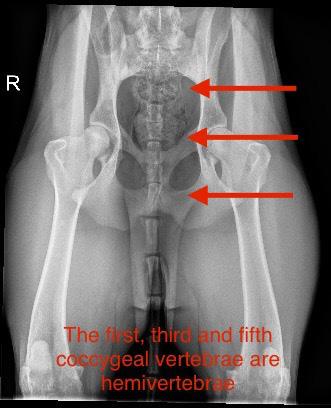

by Animal Biome (animalbiome.com) to help her alleviate the loose stools. We improved her diet, and added fish oils and other supplements. She strained to have a bowel movement from the time she got to our house as an 8 week old puppy, and has done so ever since. At first, she would walk around 10 m to complete her bowel movement. She almost “overflow defacated”. At about 10 weeks old she cried out as I was sitting on the floor playing with her and my hand bumped into her lower back. I took her to my hospital and x-rays of her back were done. She looked like a French Bulldog beyond her sacrum and into her tail. She had a pronounced wedge shaped coccygeal vertebrae (called hemivertebrae) in the location of her bump.

Ruby’s x-rays have been reviewed by a prominent ACVR member of my profession. We discussed the need to make sure she wasn’t an LTV (Lumbosacral Transitional Vertebrae)

dog, and it appears she is not. Her latest X-rays show the first, third and fifth coccygeal vertebrae are actually hemivertebrae creating a really uneven tailset area. An MRI might be in her future to help identify the reason for the pain and prolonged defecation, but not yet. She is a ‘high tail kink’ dog at this time. Kinked tails are supposed to be innocuous. But, that is not the case here. Her pain is real. My family and I will care for her and offer her a performance life as part of our pack. We lovingly call her “Aunt Ruby” already. She has had chiropractic work done and has had sporadic doses of anti-inflammatory medication if she is hurting.

Ruby in Stack Kink in tailset and her xrays